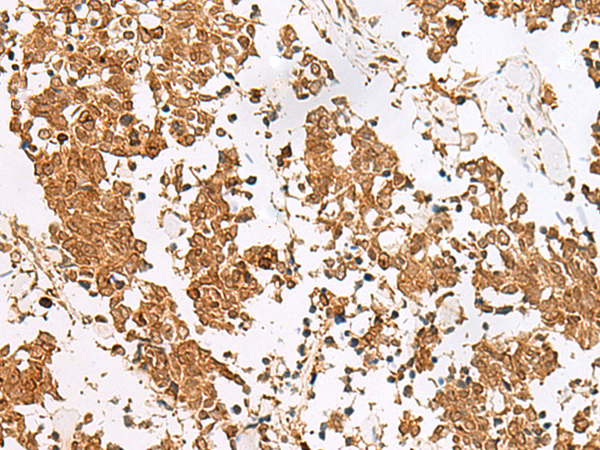

IHC positive control:

Human esophagus cancer and Human tonsil